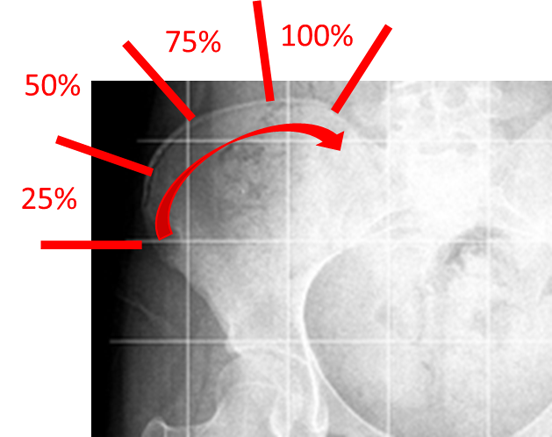

実際の診療現場では、コブ角だけでなく、骨盤の腸骨という部分の骨(お尻の部分)を見て、リッサーサインという指標を評価し、背骨の成長程度を把握しています。リッサーサインは、腸骨の上の外側から内側へ骨の成熟(骨化)が進んでいく過程をみたもので、グレート0(骨化がみられない)、グレード1(骨化が 25%)、グレード2(50%)、グレード3(75%)、グレード4(100%だが骨盤との融合なし)、グレード5(骨盤部の融合)の6つに分類されます。